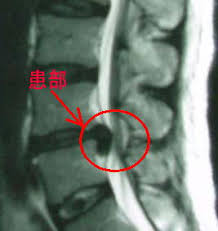

椎間板ヘルニアの典型例(私のじゃないです)